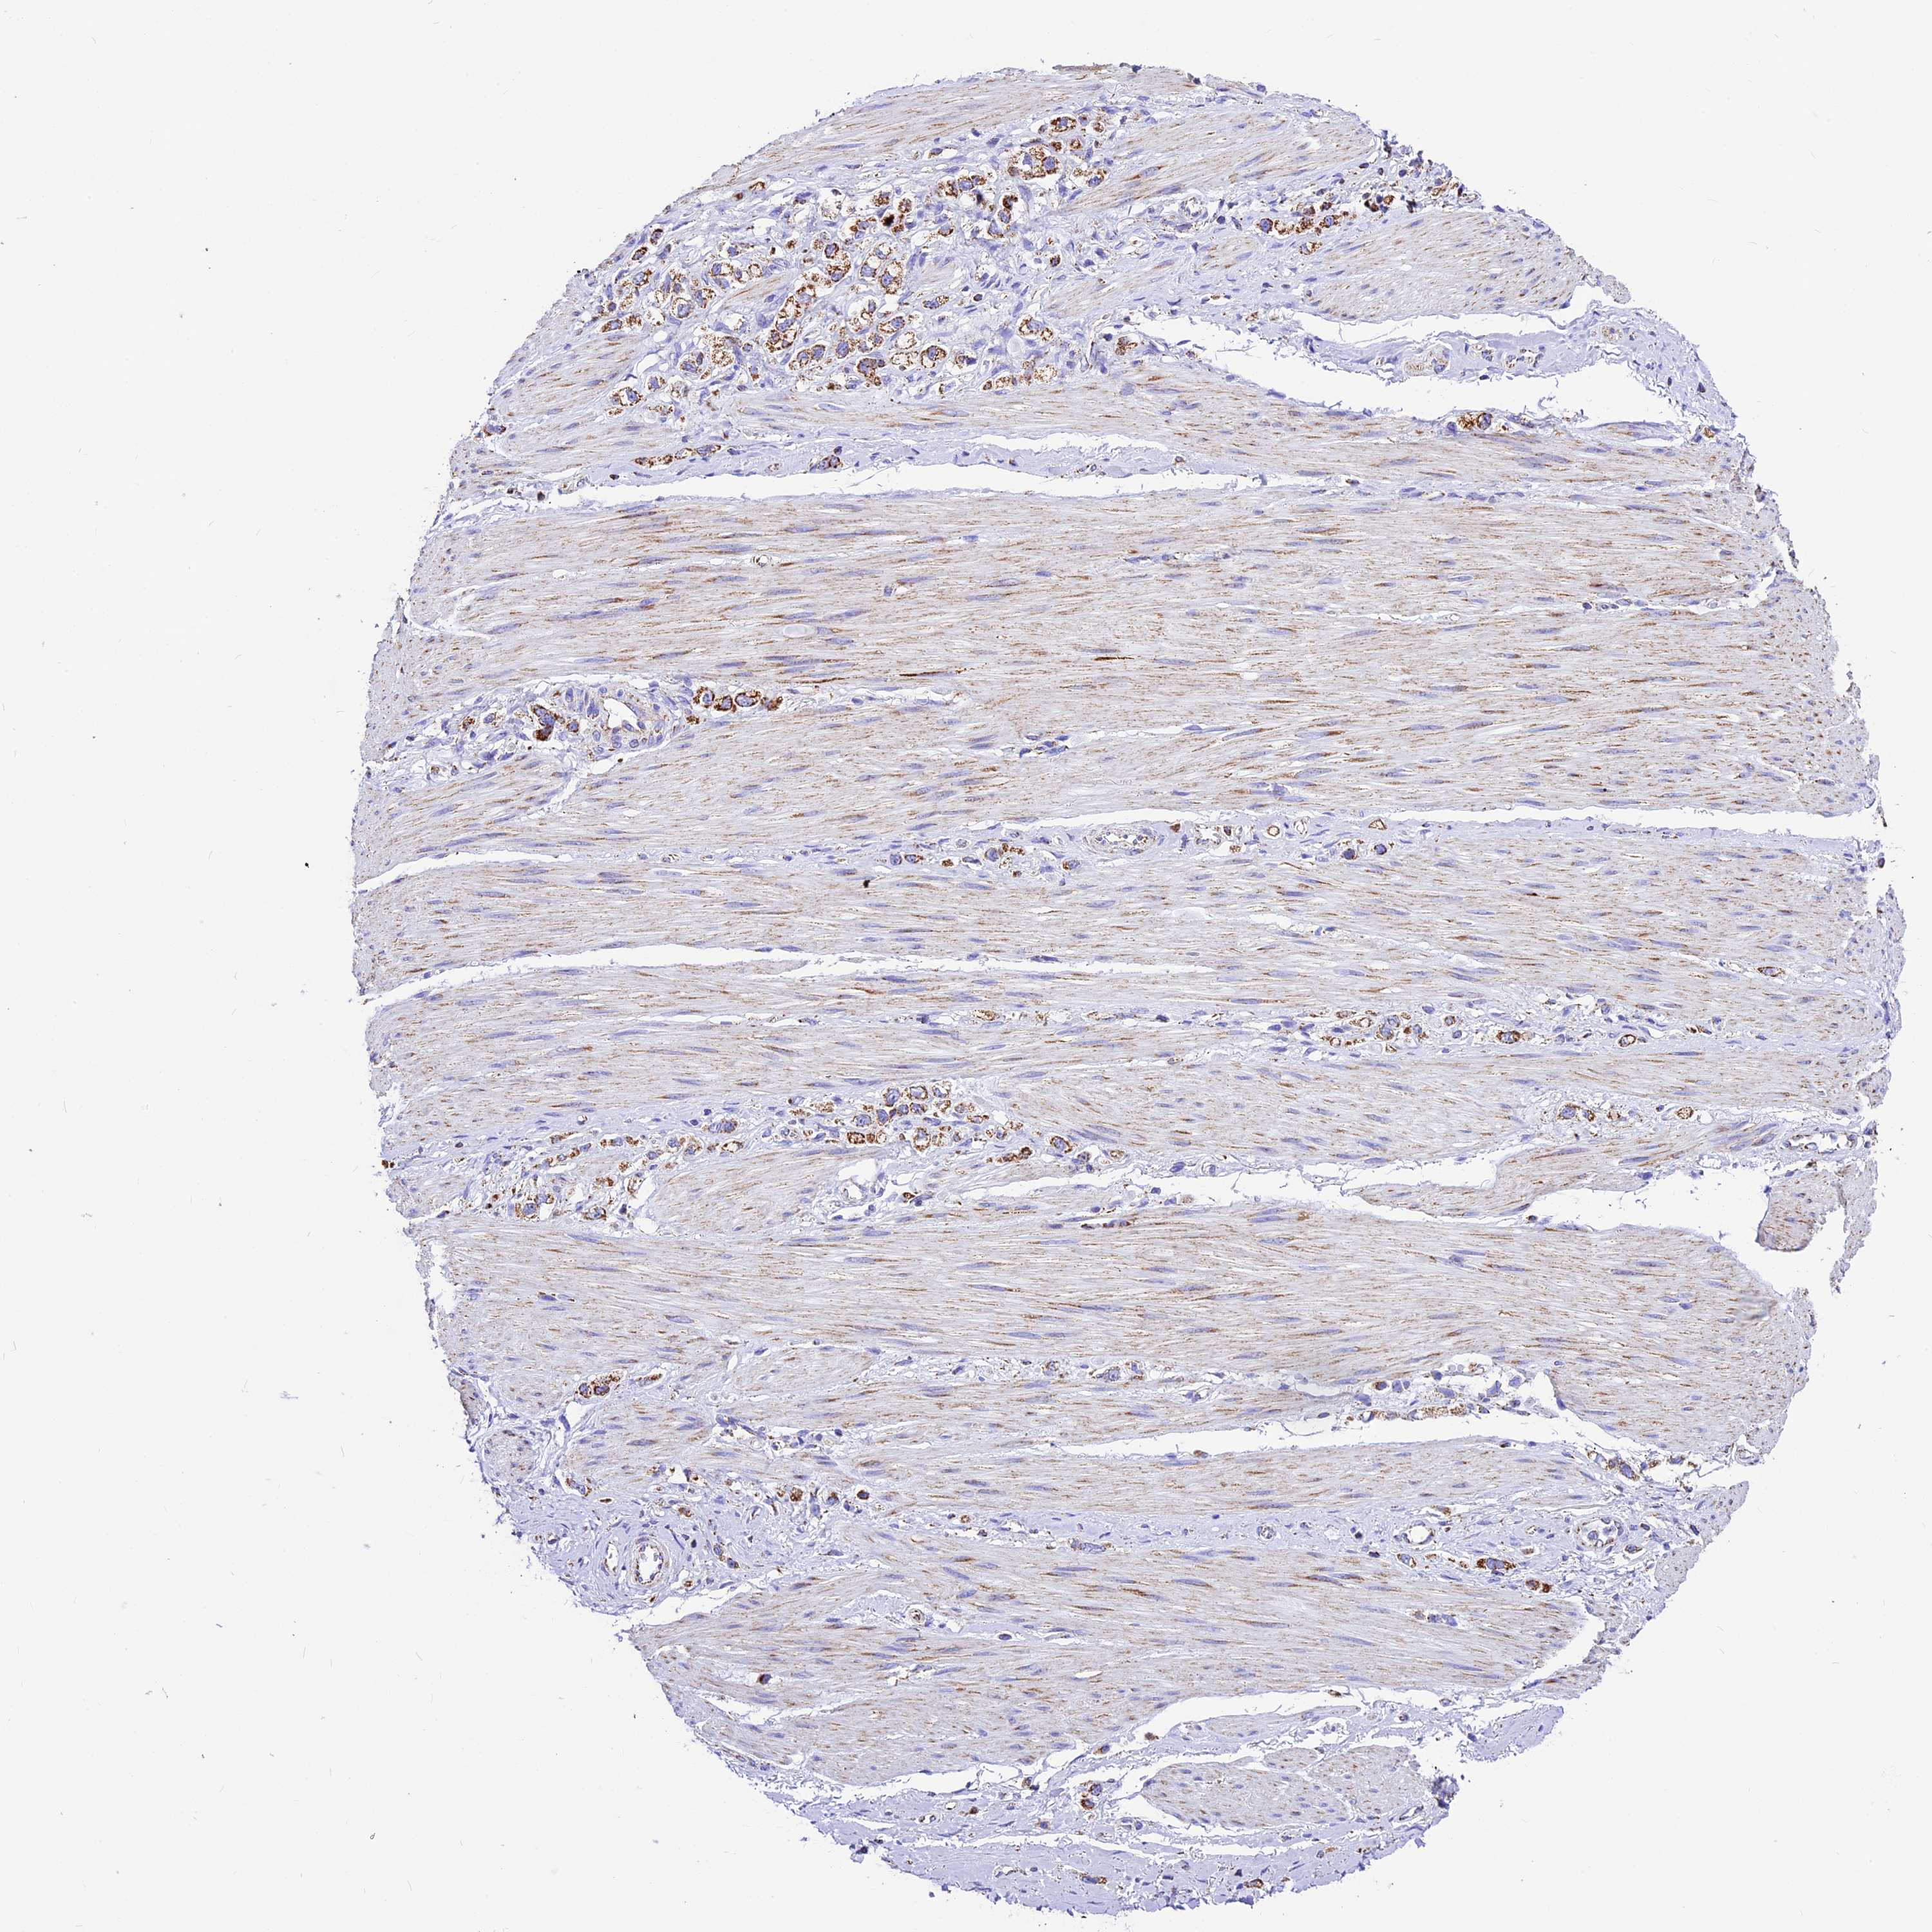

STOMACH CANCER - Protein expressioni

A mouse-over function shows sample information and annotation data. Click on an image to view it in a full screen mode. Samples can be filtered based on level of antibody staining by selecting one or several of the following categories: high, medium, low and not detected. The assay and annotation is described here.

Note that samples used for immunohistochemistry by the Human Protein Atlas do not correspond to samples in the TCGA dataset.

Antibody stainingi

Antibody staining in the annotated cell types in the current human tissue is reported as not detected, low, medium, or high, based on conventional immunohistochemistry profiling in selected tissues. This score is based on the combination of the staining intensity and fraction of stained cells.

Each image is clickable and will lead to virtual microscopy that enables deeper exploration of all samples and also displays staining intensity scores, fraction scores and subcellular localization as well as patient and tissue information for each sample.

Antibody HPA041575

Antibody HPA048098

Staining

High

Medium

Low

Not detected

Intensity

Strong

Moderate

Weak

Negative

Quantity

>75%

75%-25%

<25%

None

Location

Nuclear

Cytoplasmic/membranous

Cytoplasmic/membranous,nuclear

Adenocarcinoma, NOS